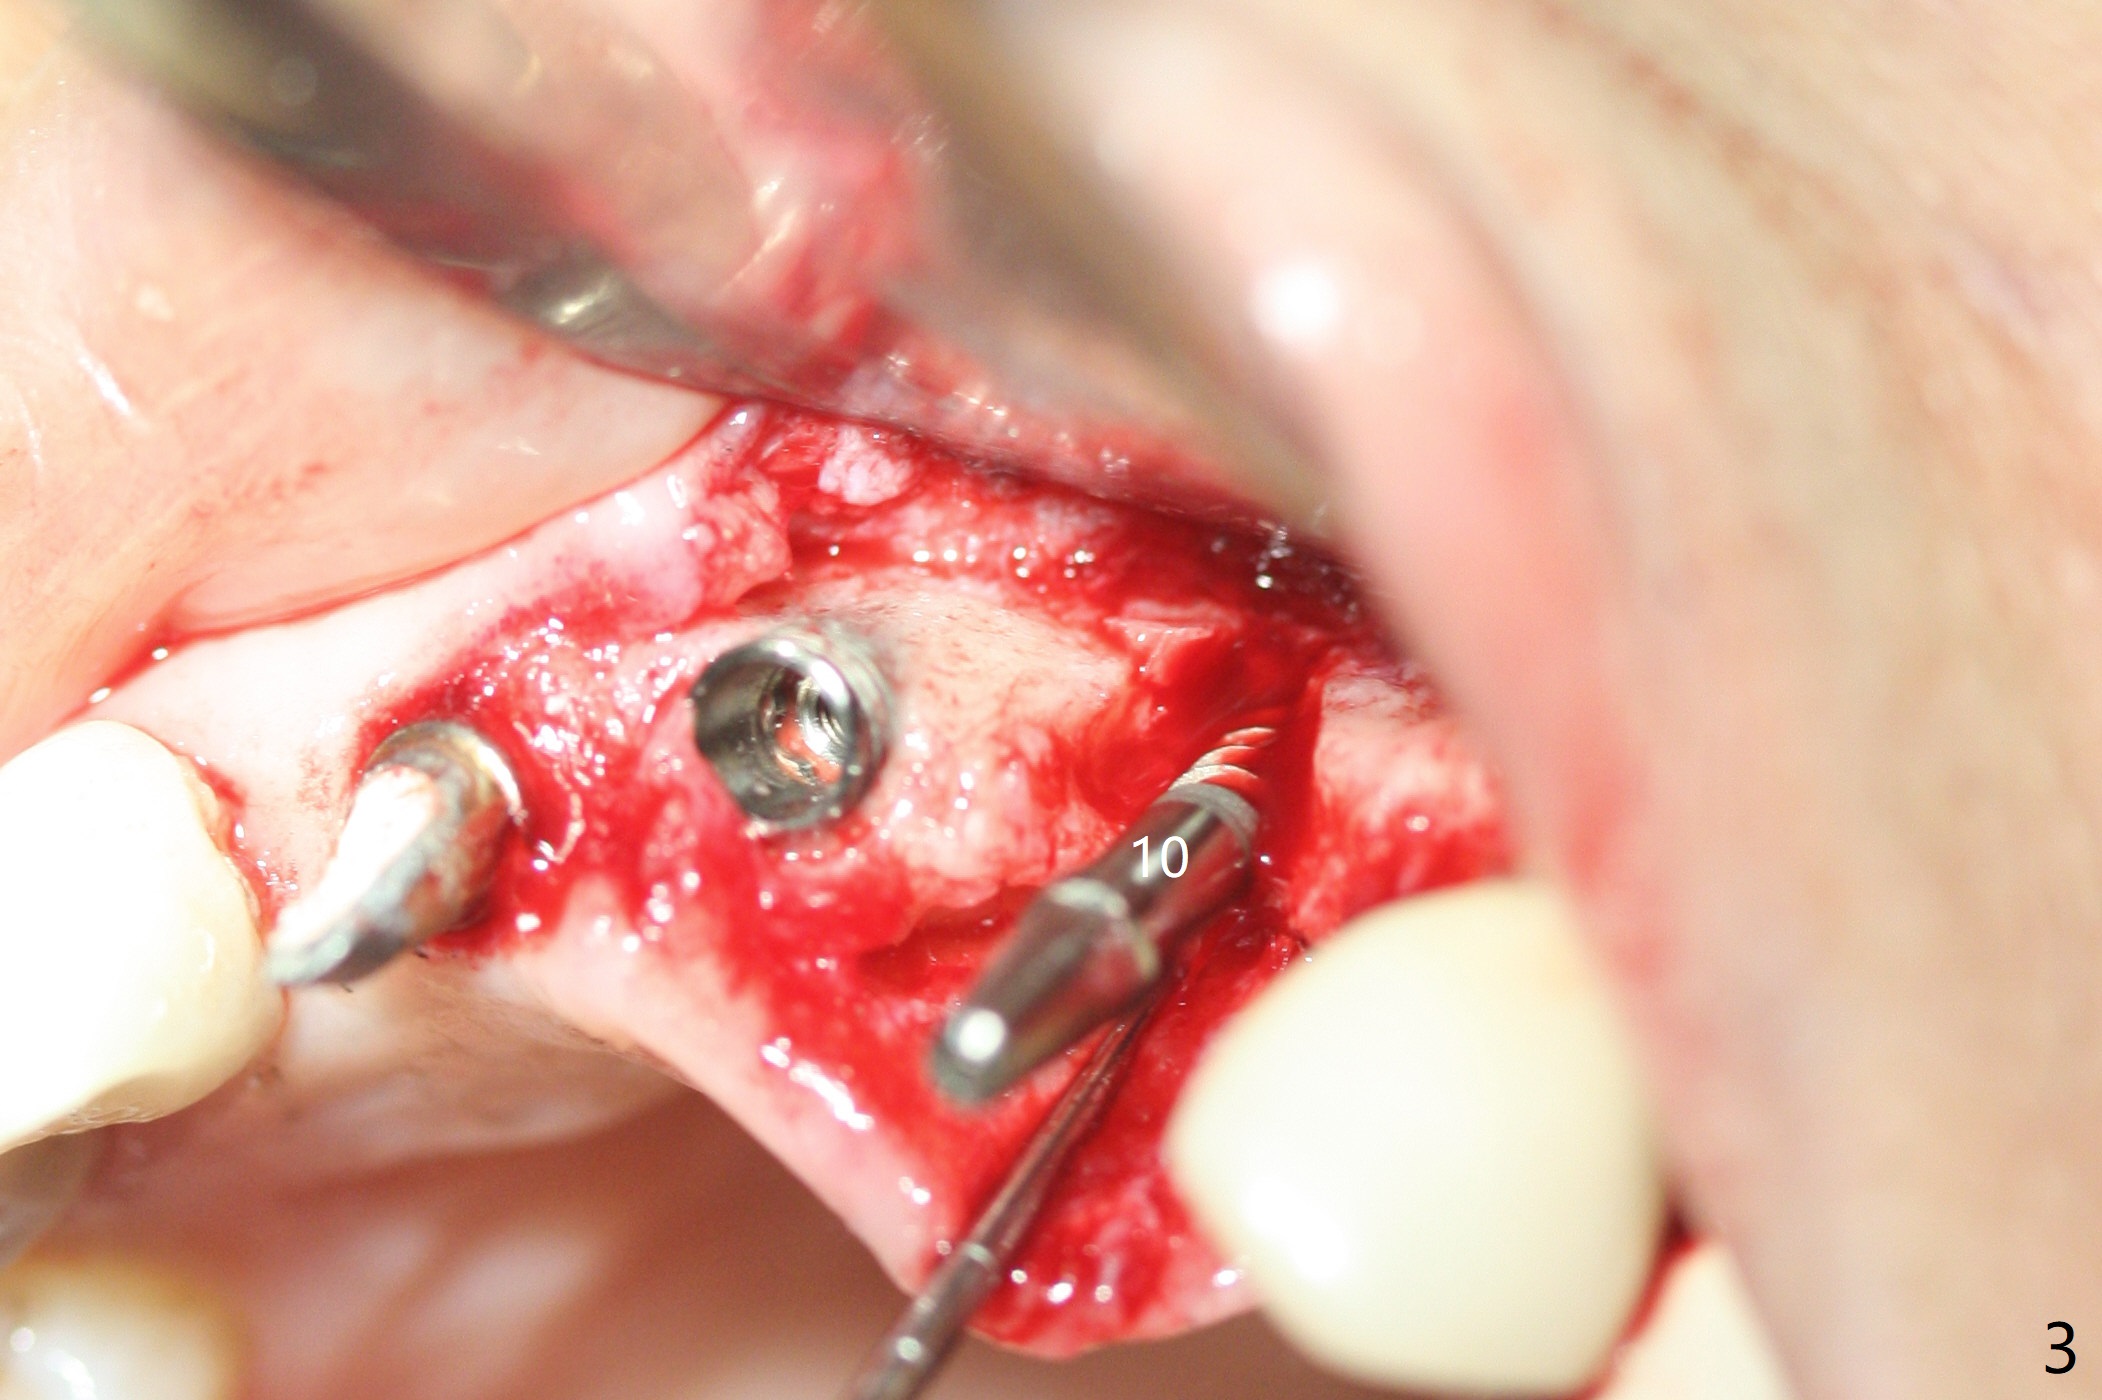

M

Incision shows exposure of microthreads at #9 and major threads at #10 due to buccal placement (Fig.1). There is bone palatal to the implant at #10 (Fig.2 P), to which a new implant will move. After implant removal, a narrower 1-piece implant (2.5x14(4) mm) is placed palatally at #10 (Fig.3,4) in combination of guide and free hand. At the site of #9 after implant removal, the guide is not used; a 3x17 mm angled 1-piece implant is placed with bad trajectory (Fig.5,6). After re-adjustment (Fig.7), the implant is placed at the right orientation (Fig.8). It appears that the guide is helpful. Allograft is placed mainly buccally (Fig.9,10 *), followed by a piece of collagen membrane (Fig.11). After tension release, flaps are approximated (Fig.12). The buccal gingiva at #9 and 10 recede nearly 2 months postop (Fig.13). Less recession at #9 is associated with more inflammation (Fig.14). The margin of the provisional is adjusted for gingival margin down growth and easy self cleaning with Water Pik (Fig.15). One month later, the gingival inflammation reduces, while there is no obvious buccal collapse (Fig.16,17). Impression is taken after laser gingivectomy nearly 4 months postop (Fig.18). While the gingiva around the implant at #9 is inflamed (periimplantitis?), the gingival cuff at #10 is well formed 5.5 months postop immediately before cementation (Fig.19). The buccal concavity at #10 is minimal (Fig.20). The gingival inflammation at #9 will be hopefully resolved after cementation of the final restorations (Fig.21). There appears to be new bone formation around the coronal implant threads 5.5 months postop (immediately post cementation, Fig.22). The microthreads at #9 may be not covered by the bone, the reason for the gingival erythema. The redness at #10 is asymptomatic 5.5 months post cementation (Fig.23). 粘固后两年牙槽嵴骨质并没有再生(图二十四),说明第一术中植体必须植入骨下(基台部分要长,否则难于修复),第二牙槽嵴处不应该有压力,植入2.5毫米植体,最后钻头应该是2.5毫米,骨下1-3毫米(尝试项目)。